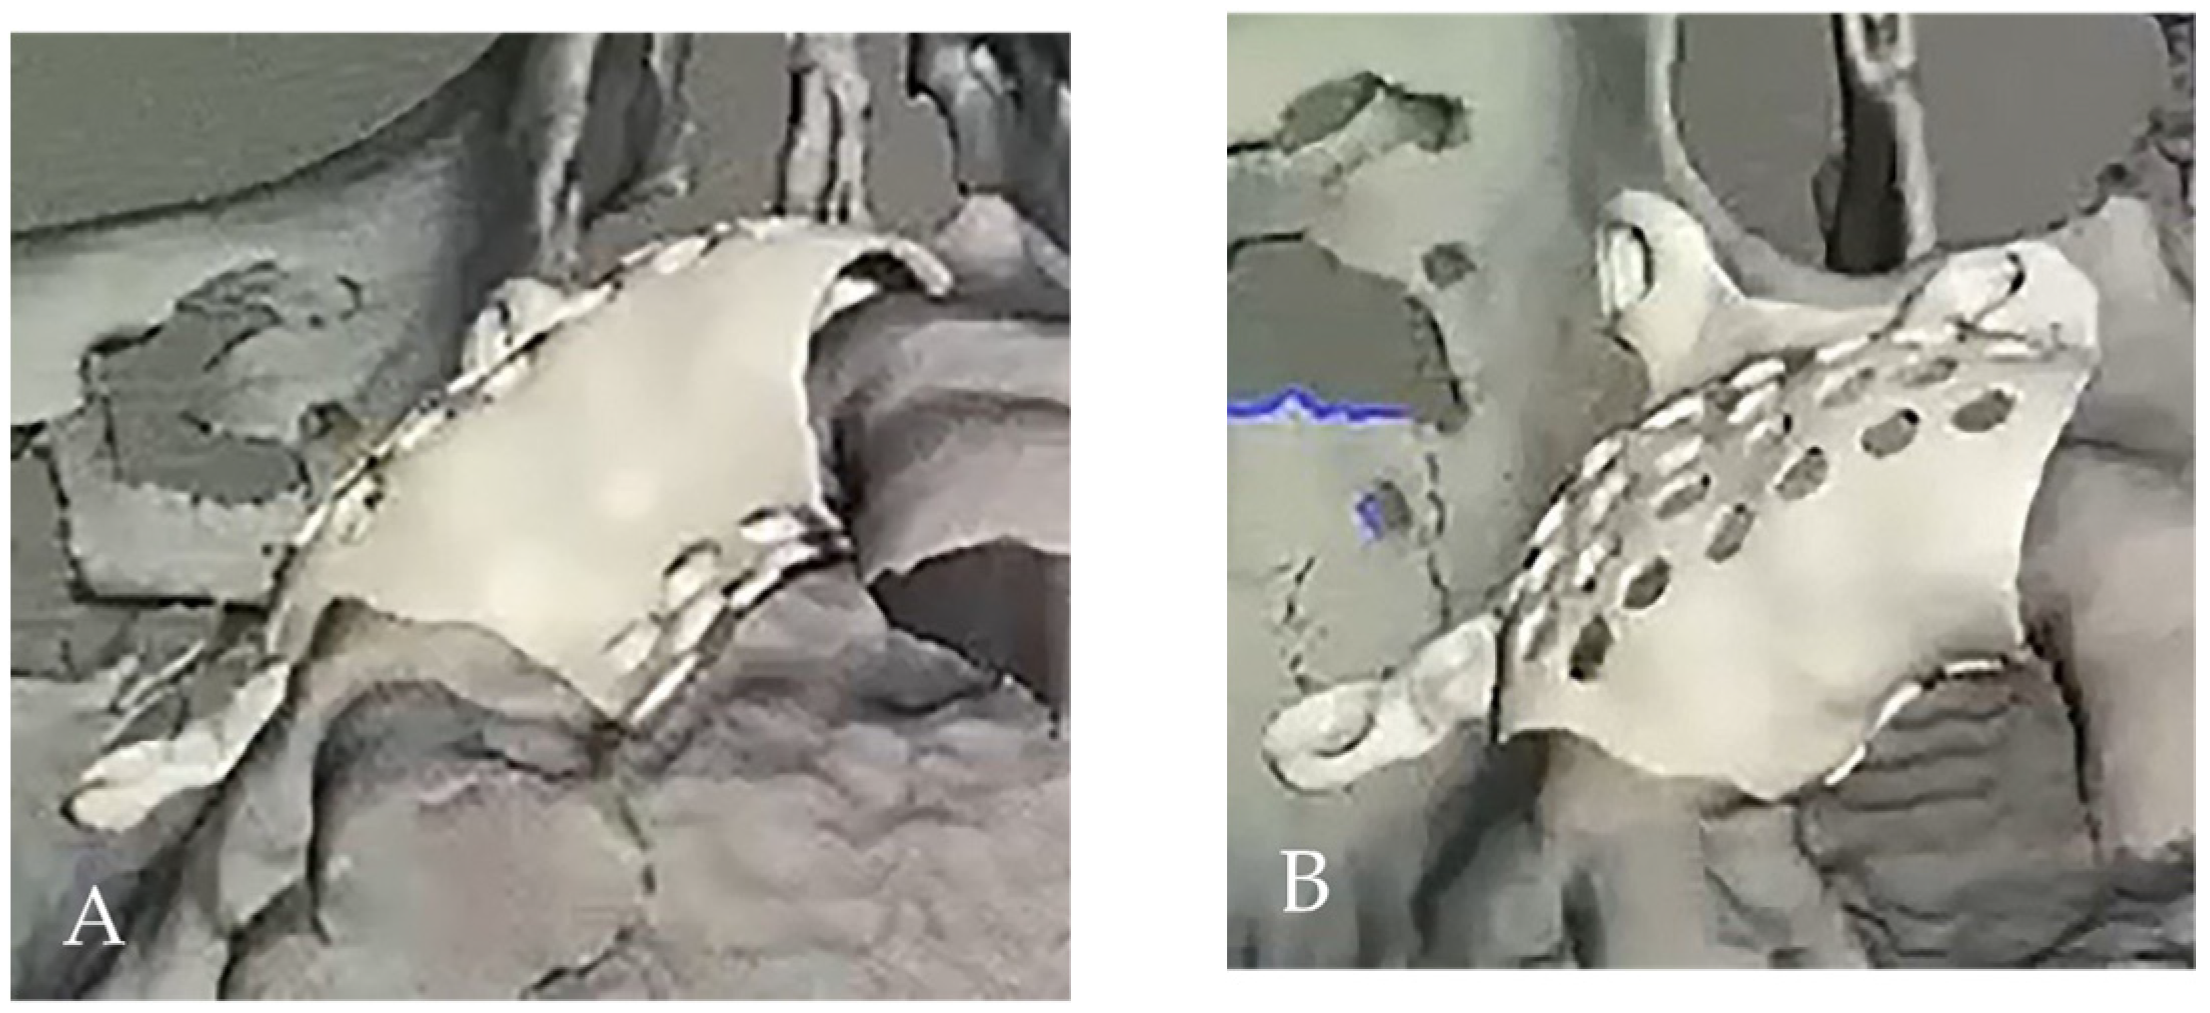

2. Case Presentation